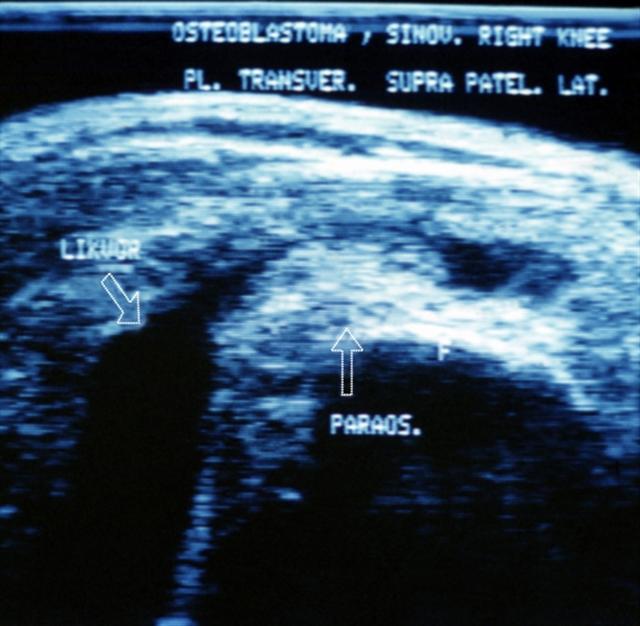

Рис. 24. Ультрасонограмма правого коленного сустава (поперечный супрапателлярный срез) при синовите: определяется скопление жидкости в верхнем завороте.